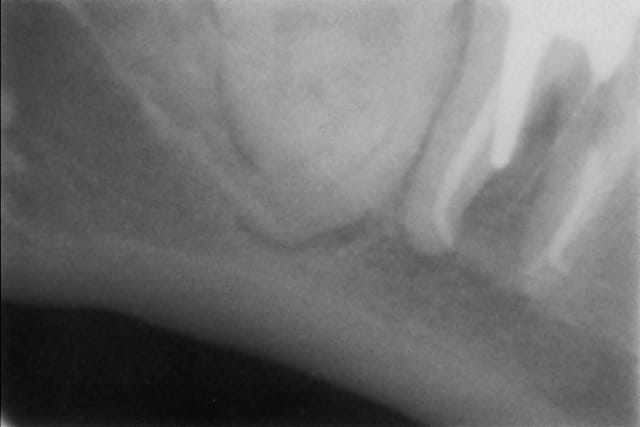

Un "vieux cas" LEONE qui se passe bien malgré des conditions de départ et de chirurgie pas au mieux! 4 ans déjà et aspect sympa très stable dans le temps. une de mes extractions implantation immédiate en site "pas idéal".La chronologie en rx.